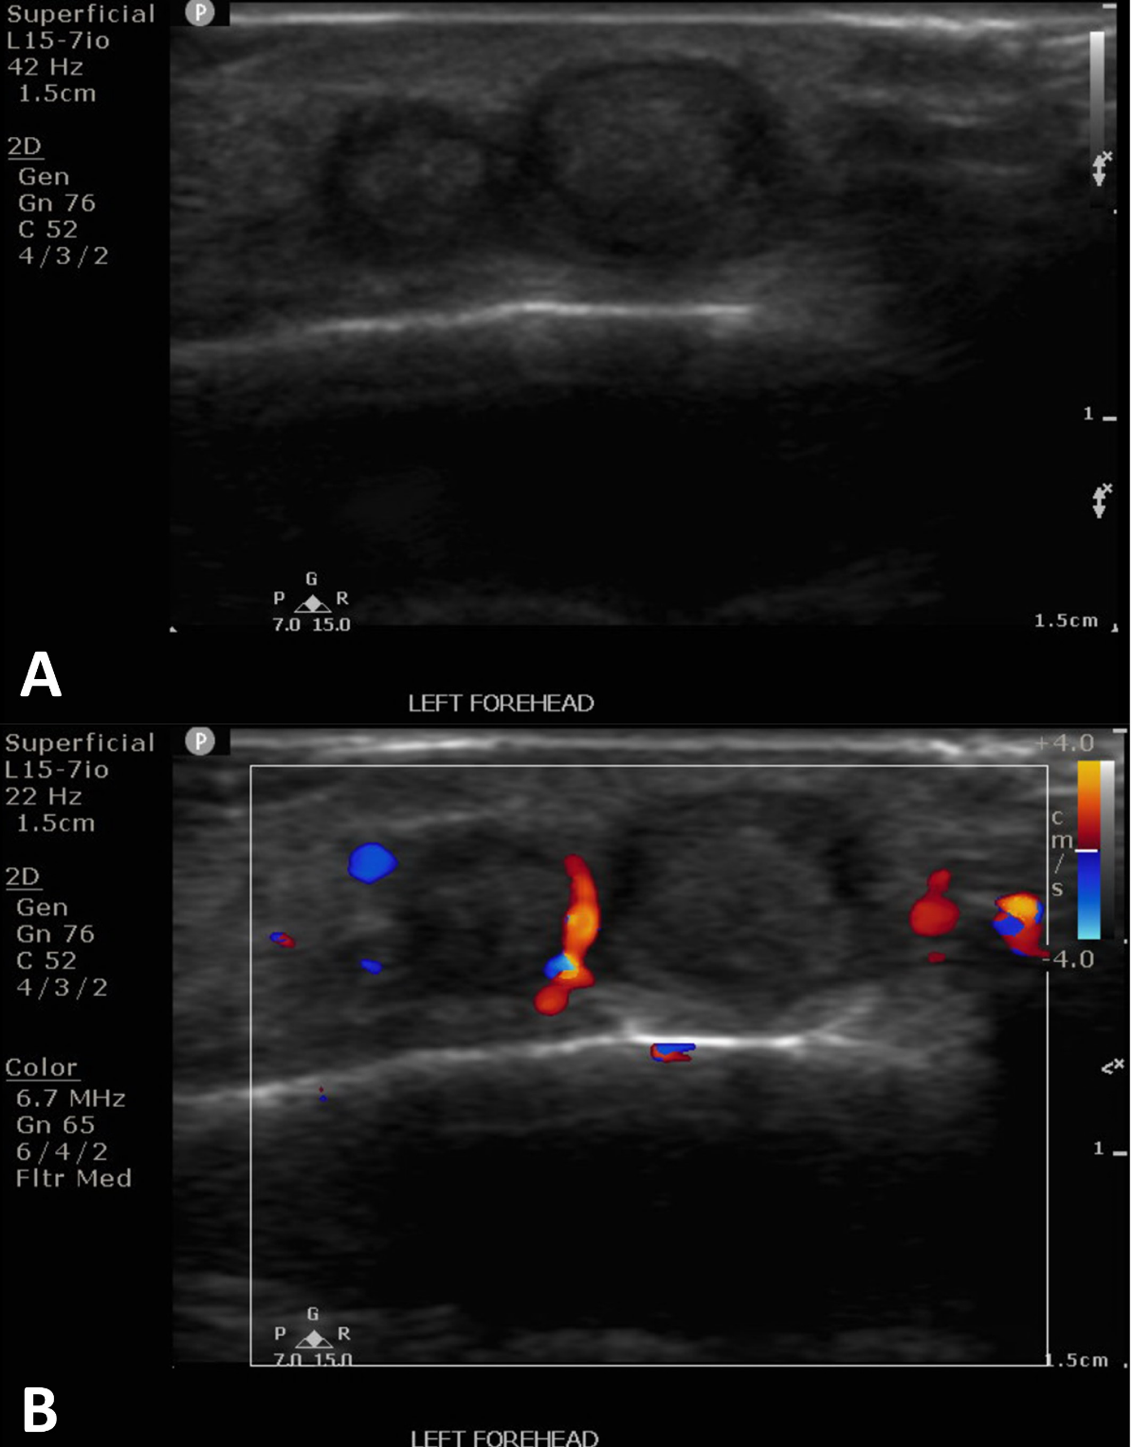

The patient is a 25-year-old male who was struck by a paintball in the left frontotemporal region, initially causing bleeding and ecchymosis. Two months later, he presented to an outpatient vascular clinic due to the development of a pulsatile mass of the left forehead (Figure 1). The clinical finding prompted a diagnostic US including arterial duplex evaluation of the site which confirmed tandem pseudoaneurysms in the scalp left of midline arising from the parent left superficial temporal artery (Figure 2).

After discussion and counseling regarding the treatment options, the patient elected to have the percutaneous procedure performed in lieu of surgery as his initial choice of treatment. The patient emphasized understanding that a surgical excision may be required in the future for complete cosmetic and symptomatic resolution. Two weeks after the ultrasound study was conducted, the pseudoaneurysms were treated with direct, percutaneous pseudoaneurysm needle access and subsequent angiogram and n-BCA glue embolization. Specific procedure details include: the procedure was performed under moderate sedation with IV administration of midazolam and fentanyl. The forehead was prepped and draped in sterile fashion and subcutaneous injection of 1% lidocaine was used for local anesthesia. Then, the pseudoaneurysm was percutaneously accessed with a 21-gauge needle under direct US guidance. Angiography through the needle demonstrated successful access to the pseudoaneurysm; which was located at a branch point of the STA. Further angiographic opacification of the vascular territory demonstrated two additional small pseuaneurysms, one arising from each branch (Figure 3).

There was normal venous drainage on the scalp and no evidence of intracranial communication. Embolization with n-BCA glue was then delivered under fluoroscopic guidance. The glue embolized all three pseudoaneurysms including a short segment of the parent inflow artery and short segments of the outflow arteries. The glue cast was well visualized on fluoroscopy. Post-intervention ultrasound confirmed thrombosis of the pseudoaneurysms (Figure 4). The patient tolerated the procedure well without complications.